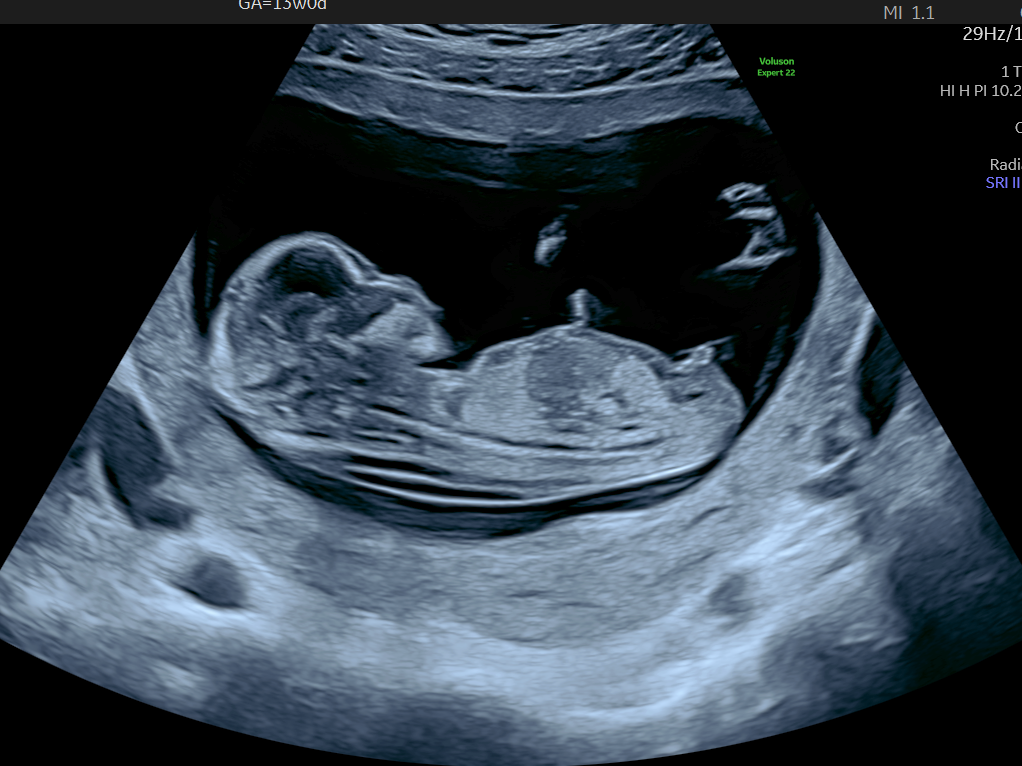

超音波検査は妊娠7週から8週目以降に実施され、性別判定の基本的な手段である。特に、妊娠12週を過ぎると、胎児の性別の外部特長が明確に見えるようになる。以下のポイントが超音波検査の特徴である。

- 妊娠12週: 超音波検査によって性別の外部特長が明確に見える。

具体的なデータによると、超音波検査の精度は、妊娠12週以降に約95%となります。この時期には、性器の外観が明確になり、正確な判定が可能です。血液検査はさらに高精度で、約99%の確率で性別を明らかにします。実際のケーススタディでは、妊娠10週の時点で行った血液検査により、多くの親が早期に性別を確認できたと報告されています。